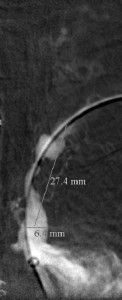

The 4 images you see above were recorded by me during primary stenting of irregular atherosclerotic stenosis of the left subclavian artery in a 54-year-old hispanic female who was referred to my interventional radiology clinic for management of the stenosis. She had presented to her primary care physician with symptoms of hindbrain ischemia upon using her left upper limb and earlier workup confirmed left subclavian arterial stenosis. The 2 top images illustrate the character and severity of her disease, the first image in the bottom row shows the process of balloon-expandable stenting of the disease, while the 2nd image in the bottom row reveals complete elimination of the stenosis and reappearance of the left vertebral and internal mammary arteires, which were invisible on the pre-intervention angiograms reflecting the severity of the stenosis.